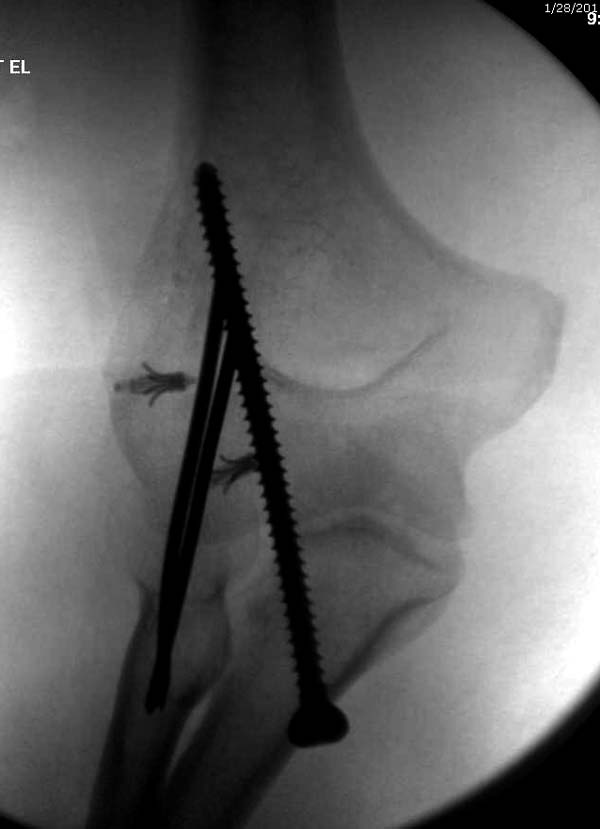

Несмотря на отрицательный отзыв, некоторые нестабильные вывихи лечим трансартикулярным методом. Тонкие спицы ломаются и имеют риск внутрисуставной инфекции. Винты 3.5 мм не выдерживают, а более толстые каннюлированные винты неплохо проявили себя. Неосторожность при установке приводила к поломке тонких guide wire внутри сустава. Лучшие кортикальные в 4.5 мм и гипс на три недели. Винт удаляется, затем разработка сустава.

Иногда гипс не гарантировал стабильность и винт внутри гипса ломался. Удаление сломанного винта облегчаем, оставляя на пару мм длиннее с наружной стороны, Т.е винт через олекранон над наружный мыщелок, и никогда в трубку диафиза! Из малого разреза кончик сломанного винта удаляется без проблем.

В заключение: результат применения трансартикулярной фиксации (более 20 лет) в сравнении со сложными реконструктивными операциями показывает лучшую амплитуду движений! Возможно, у коллег имеются другие варианты, а мы без привлечения больших затрат решаем проблему.

Для примера здесь случай начатый в другом центре, а потом переправленный к нам.

Снимки: 1-2 вывих, 4-5 вторичное смещение в гипсе, реконструкция латеральной связки и капсулы 13-14, повторный вывих после реконструкции, перевод в наш центр; 18-21 временная фиксация, 22-25 трансартикулярная фиксация и нестабильная головка фиксирована спицами, 29-30 амбулаторно, 32-33 после удаления винта и спиц...